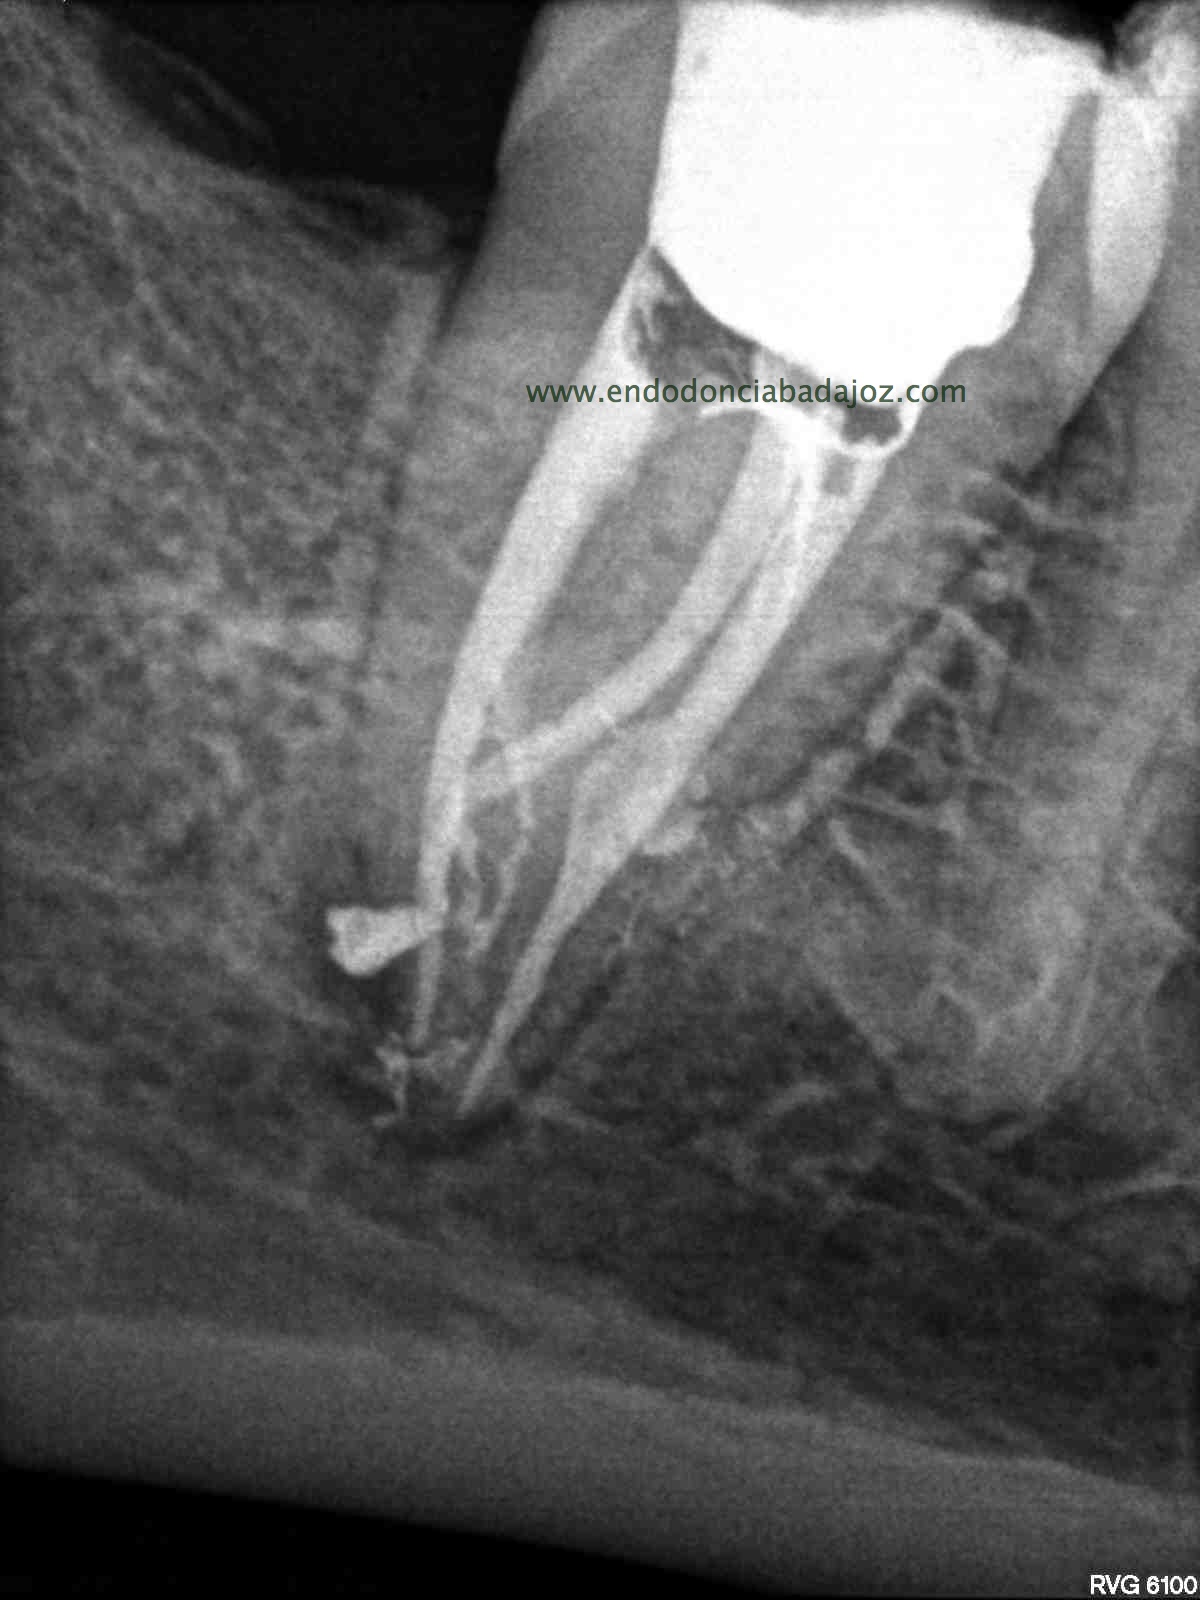

Sistemas de Conductos de un 4.7

Nos remiten a  la clínica una pieza 4.7, con necrosis pulpar y afectación periodontal, periodontitis apical:

La anatomía de los conductos nos hacia sospechar de un caso algo más complicado. Lo más complicado fue mantener la permeabilidad de los conductos. Instrumentamos con sistema rotatorio de Mtwo, mucha irrigación, se usó Irrisafe en los últimos lavajes, y como sistema de obturación usamos Condensación vertical con ola contínua, haciendo un backfilling con la Pistola Obtura II.

1. En los últimos lavajes??? hay Dr. Nieto cuántas influencias tiene usted.. Una vez más, hace que me enorgullezca tener un amigo así…eres un crack. cómo me gustaría saber que anatomía interna tiene este molar, y cuántas salidas tiene…hace donde irán esos conductos laterales presentes en los tres conductos? Qué difícil es manejar este caso, y lo importante que es no tener prisa por preparar el tercio apical en este tipo de curvaturas. Un abrazo…